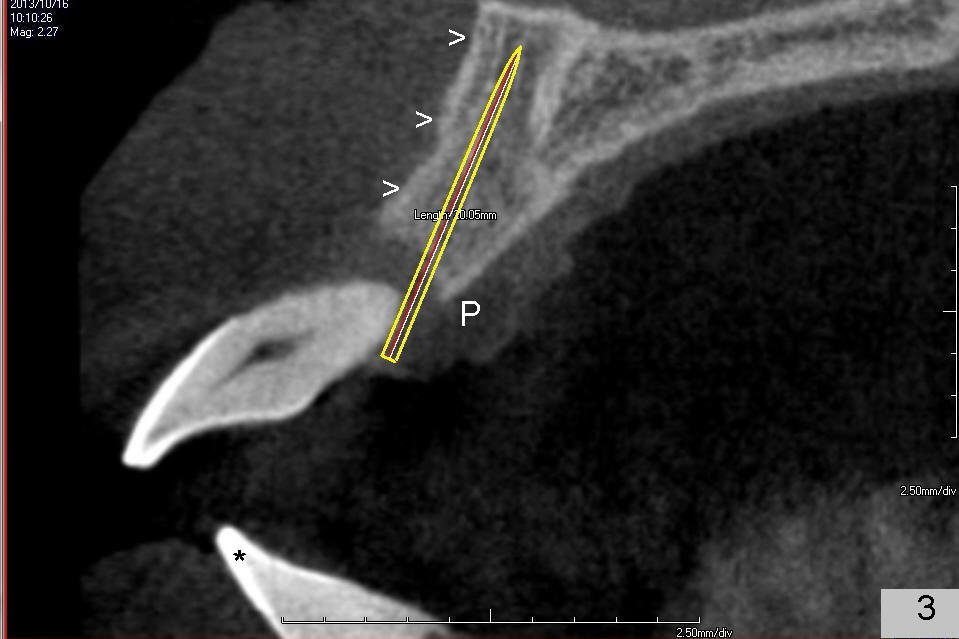

A 49-year-old man has severe chronic periodontitis. The upper central incisors are protrusive and mobile (Fig.1,2: #8,9), but the basal bone is wide and tall (BB in Fig.2). Immediate implants are going to be placed. To avoid malpositioning of the implant, initial osteotomy begins close to the palatal plate (Fig.3: P), while the axis of the osteotomy is parallel to and close to the buccal plate (>). The implant (Fig.4 pink), abutment (red) and the crown (white) will be in a favorable trajectory. To reduce protrusion, the incisal edge of the lower central will be trimmed (compare Fig.3 * and Fig.4 black area).